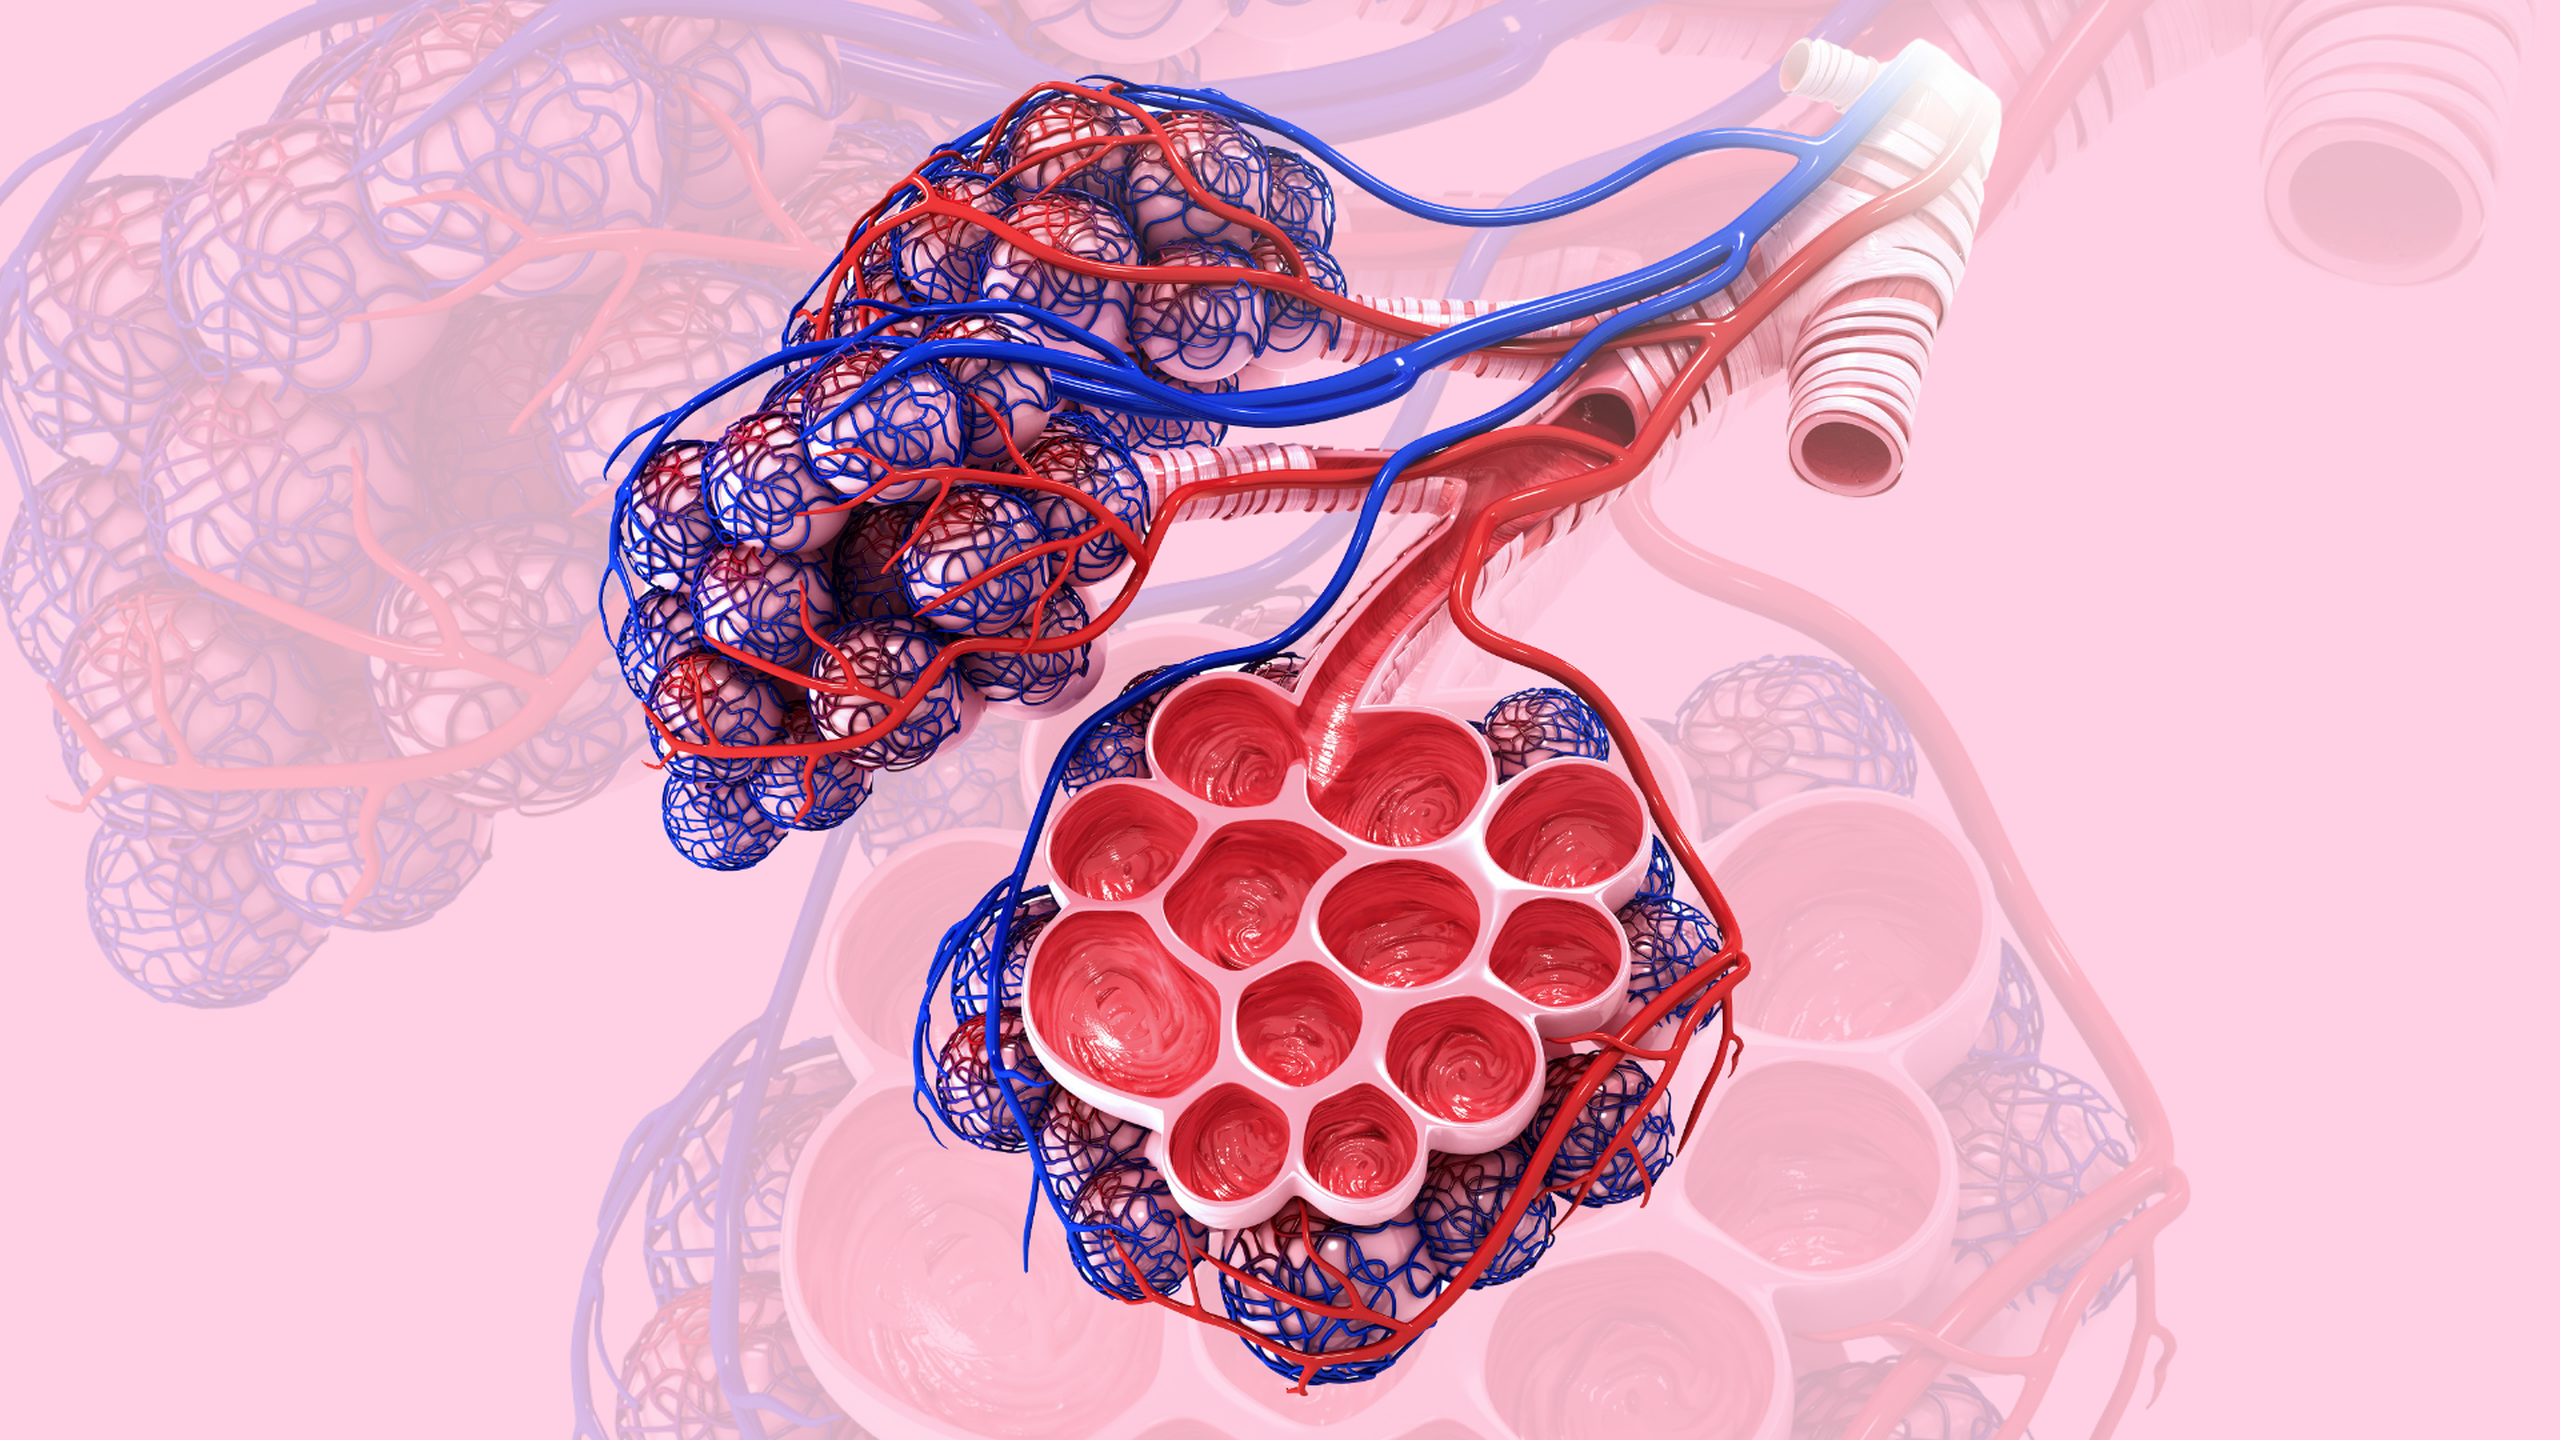

Xẹp phổi: Bệnh lý xảy ra ở đường hô hấp khi phổi hoặc các thùy phổi rơi vào trạng thái bị xẹp một phần hay toàn bộ dẫn đến các túi nhỏ phế nang không giãn nở như bình thường khi cơ thể thực hiện động tác hít - thở mà có chiều hướng bị xẹp (giảm thể tích) hoặc chứa đầy dịch.